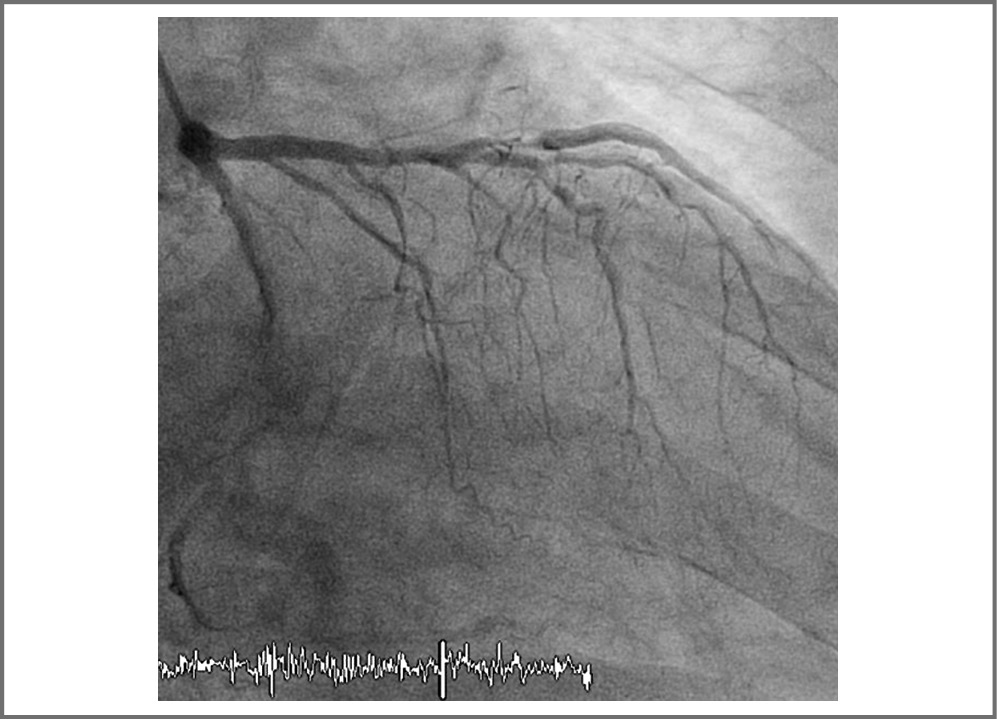

Пациент госпитализирован в региональный сосудис- тый центр. В связи с отсутствием признаков реперфузии на ЭКГ выполнена экстренная коронароангиография (КАГ), при которой выявлена окклюзия передней нисходящей артерии (ПНА) в проксимальном сегменте. Одномоментно выполнено ЧКВ со стентированием ПНА двумя стентами с лекарственным покрытием (рис. 1, 2). Процедура прошла без осложнений, кровоток по ПНА после вмешательства – TIMI III. По данным ЭКГ после вмешательства отмечаются признаки реперфузии в виде снижения элеваций сегмента ST.

Рис. 1. КАГ: до ЧКВ.